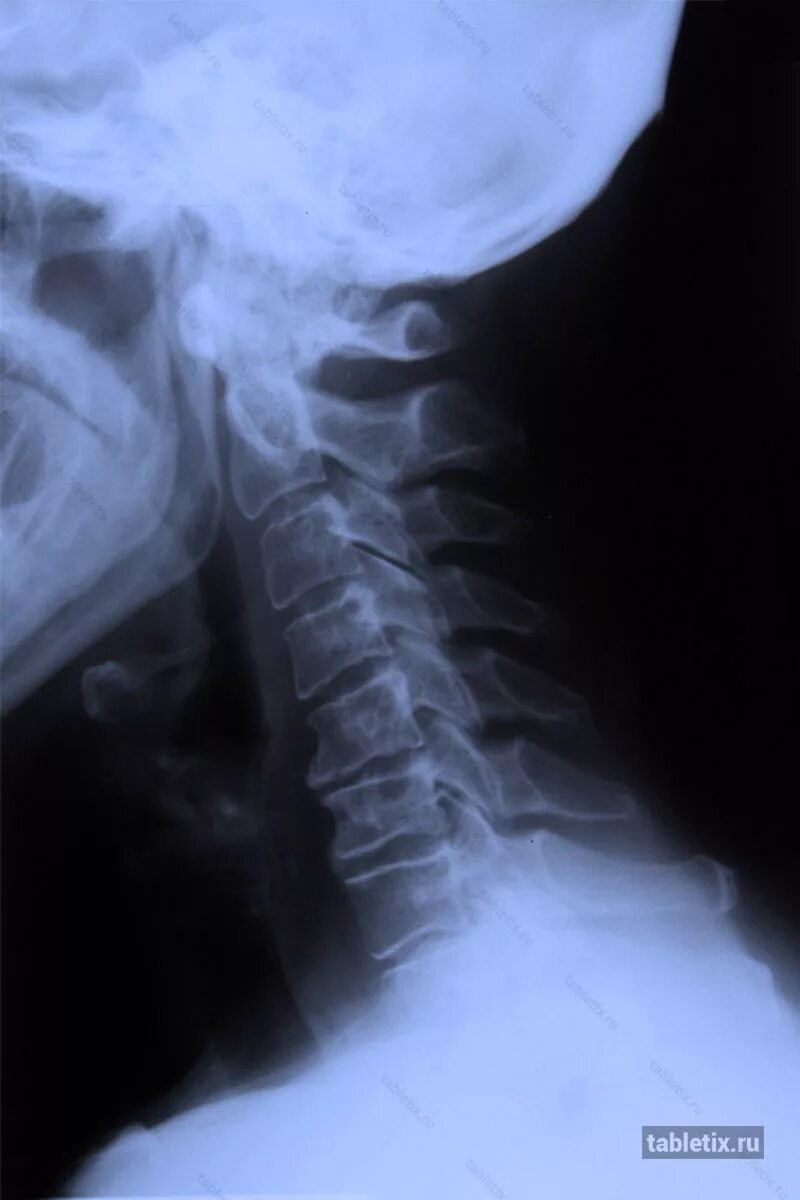

Остеофит симптомы